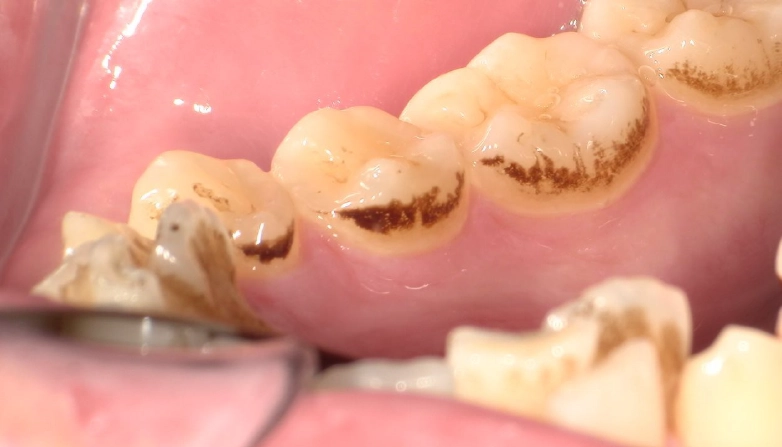

症例3

before

after

| 主 訴 | 着色を落としたい |

| 治療期間 | 通院 1回 |

| 治 療 費 | 1回 7,700〜11,000円(税込) |

| 治療内容 | PMTC |

| 治療のリスク | 歯自体の色を白くすることはできない。 しばらくすると再び着色することがある。 |